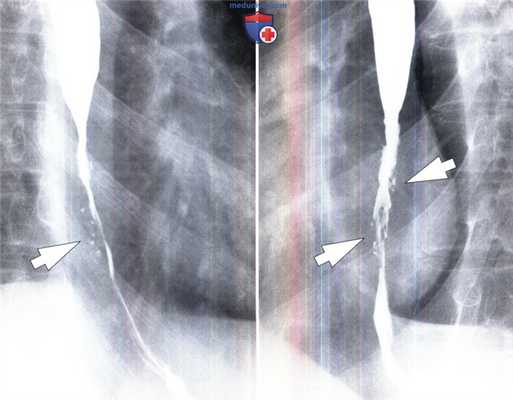

Идиопатический эозинофильный эзофагит может проявляться сегментарными стриктурами в верхней или средней частях пищевода. Стриктуры содержат множественные тесно расположенные концентрические кольцевидные углубления, в результате чего формируется так называемый «кольцевидный» пищевод (Zimmerman et al., 2005). Возможны развитие диффузного сужения пищевода, приводящего к уменьшению его просвета, а также нарушения моторики пищевода.

Идиопатический эозинофильный эзофагит у мужчины 21 года.

На рентгенограмме выявлено диффузное неравномерное сужение просвета (указатели) в нижней половине пищевода с дилатацией в проксимальном отделе и нарушением пассажа.